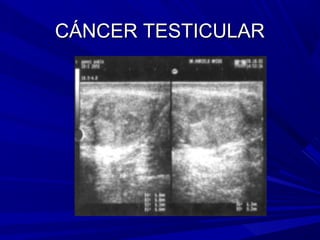

CÁNCER TESTICULAR

Es la neoplasia más frecuente entre los varones de 15 a 35 años

CÁNCER TESTICULAR Es laneoplasia más frecuente entre los varones de 15 a 35 años Testículo normal: está conformado por túbulos seminiferos dispuestos en 200 a 300 lóbulos y túbulos rectos colectores, envuelta por la túnica albugínea. Los túbulos rectos forman la rete testis que desembocan en los conductos eferentes: estos conectan al testículo con el deferente. Los túbulos seminíferos contienen dos poblaciones celulares : las células de Sertoli y las células germinales (espermatozoides). En el intersticio testicular se encuentran dispuestos en racimos las células (intersticiales) de Leydig productora de andrógenos. Las neoplasias primarias surgen de cualquier componente celular